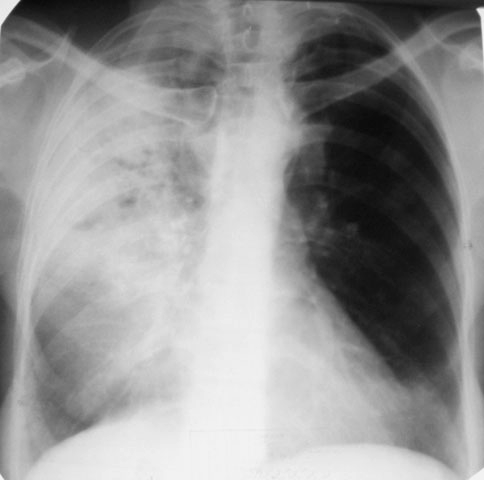

Рентгеновские снимки при пневмоцистной пневмонии